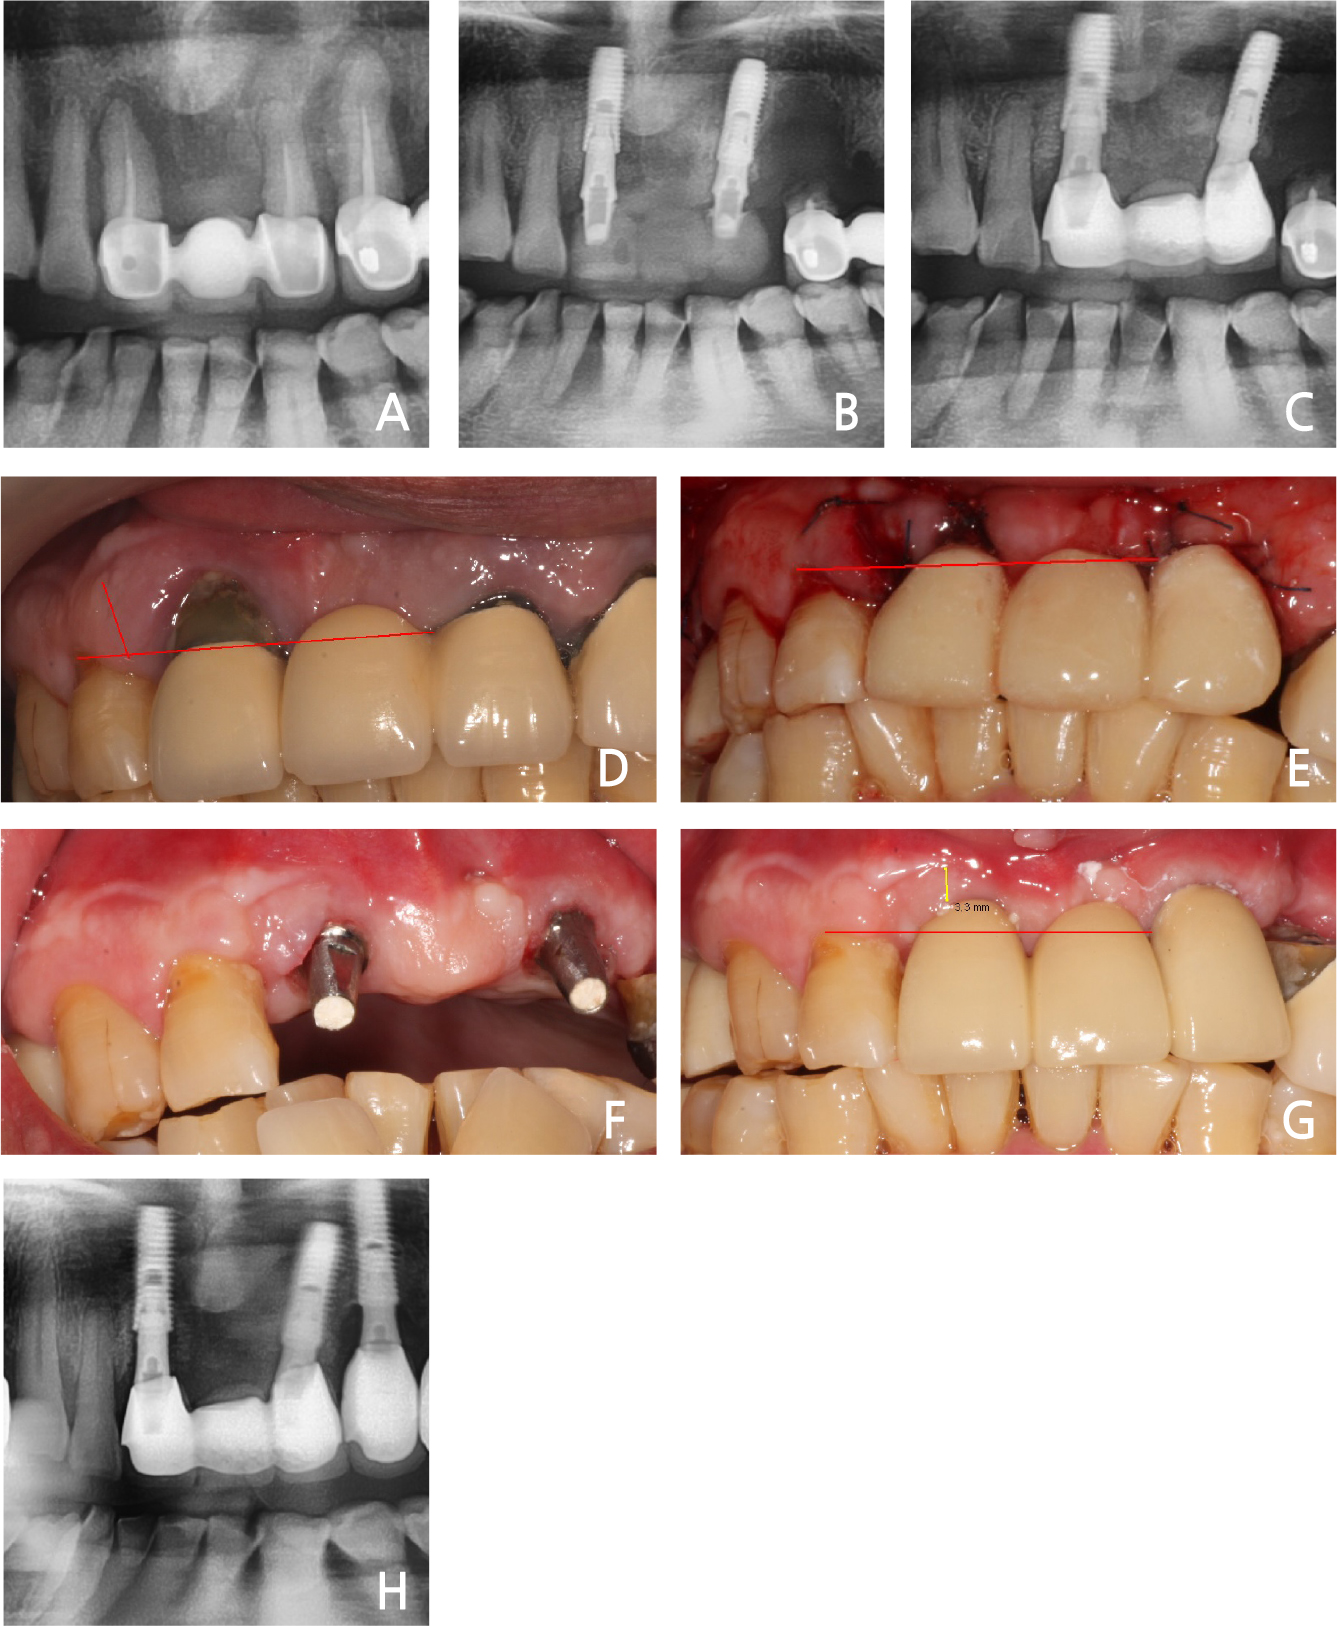

A 56-year old man presenting with the chief complaint of the severe pain on the anterior maxilla visited our dental clinic. Clinical and radiographic evaluations showed severe bone loss and purulent

exudates in the right maxillary incisor and the left molar area. The patient just wanted the treatment of the anterior maxilla area (Fig. 7A). The right maxillary incisor and left maxillary lateral incisor were therefore extracted. Immediate implant placement and bone graft were performed (Fig. 7B). The rotation flap of the distal gingiva on the right lateral incisor was performed (Fig. 7E). The primary stability was attained from the apical intact bone area. A provisional crown was made immediately after implant placement (Fig. 7E). Three weeks later, a final prosthesis was inserted. The gingival height and attached gingiva were preserved (Fig. 7G). After 3-years, the abnormal condition was not shown in the panoramic view (Fig. 7H).

Fig. 7.

(A) Bone resorption on the maxilla anterior area, (B) Immediate implant placement with bone graft, (C) Final loading after 2 weeks, (D) Preoperative gingiva recession on the right maxillary incisor, (E) Postoperative immediate provisional crown (#12 distal proximal gingiva rotational flap for the attached gingiva), (F) Gingival healing after two weeks, (G) Maintained gingiva tissue after 3 weeks postoperatively (final restoration, red arrow: about 3 mm of attached gingiva), (H) Panoramic view of the 3-years follow-up.